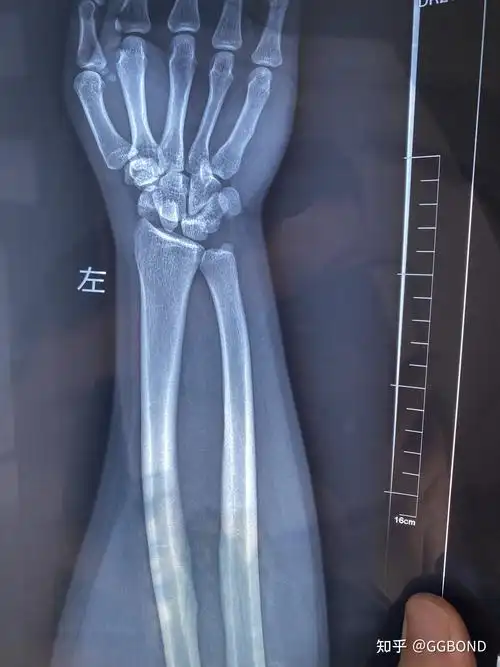

舟骨三角骨骨折及月骨周围脱位 - 知乎